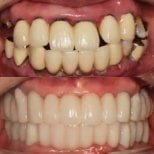

- Check reviews and patient photos. Look for real before-and-after cases and feedback from international patients.